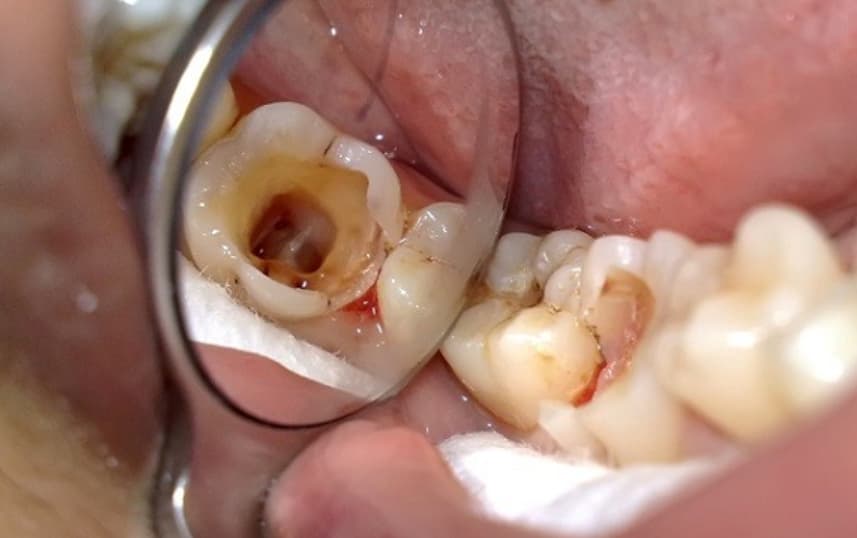

Tủy răng là nơi nuôi dưỡng và suy trì sự sống của răng. Khi tủy bị chấn thương, viêm nhiễm sẽ gây ra các cơn đau dữ dội và khó khăn khi ăn nhai. Khi phát hiện tủy bị viêm các bác sĩ sẽ chỉ định bạn lấy tủy. Mục đích của thủ thuật này sẽ giúp lấy hết tủy tổn thương, loại bỏ vi khuẩn gây hại, ngăn ngừa nhiễm trùng và giúp giữ lại tối đa răng thật.

Nếu răng mới chớm viêm tủy việc điều trị sẽ diễn ra nhanh chóng, chi phí thấp. Ngược lại răng bị viêm nặng, có mủ hoặc lan ra vùng nướu, xương hàm thì cần xử lý kỹ hơn. Trường hợp này sẽ phải điều trị nhiều lần hoặc kết hợp với thuốc làm phát sinh thêm chi phí.

Bước 3: Mở tủy, xử lý viêm và tạo hình lại ống tủy. Bác sĩ sẽ tiến hành mở tủy, loại bỏ hoàn toàn phần tủy bị viêm nhiễm, làm sạch và tạo hình ống tủy.

Tủy răng bị viêm nhưng không được chữa trị sớm theo thời gian sẽ dẫn đến những biến chứng sau:

Khi tủy răng bị viêm mà không điều trị kịp thời vi khuẩn có thể di chuyển ra các mô quanh răng gây viêm nướu, viêm quanh chóp. Thậm chí là thâm nhập vào máu gây ra các bệnh lý như tim mạch, tiểu đường, viêm màng não…

Tủy bị tổn thương nghiêm trọng sẽ khiến răng chết dần. Nếu không được xử lý, răng có thể lung lay và cuối cùng mất răng.

Viêm tủy kéo dài có thể hình thành ổ mủ dưới chân răng gây đau nhức dữ dội, sưng mặt, sốt và mệt mỏi. Áp xe không được xử lý đúng cách có thể dẫn đến hoại tử mô hoặc nhiễm trùng nặng.

(Nhiễm trùng, sâu răng lan rộng, áp xe chân răng, răng lung lay là những biến chứng có thể gặp nếu không điều trị tủy sớm)(**)